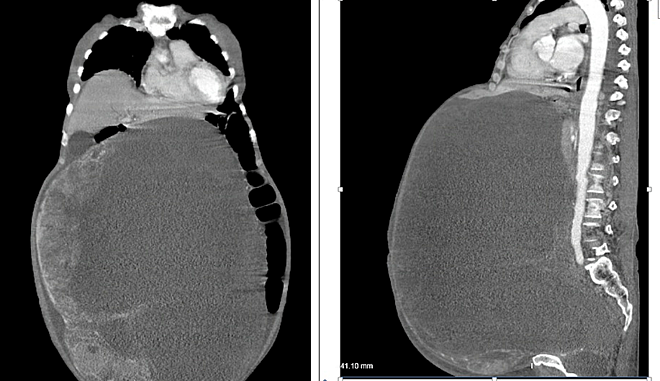

Hình ảnh X-quang cho thấy khối u chiếm gần hoàn toàn ổ bụng bệnh nhân.

Các bác sĩ hội chẩn liên khoa, tiến hành mổ cắt khối u vào ngày 19/3. Cuộc phẫu thuật khá khó khăn do u quá lớn, kích thước khoảng 30x50 cm, nặng 30 kg, dính vào ruột và thành bụng.